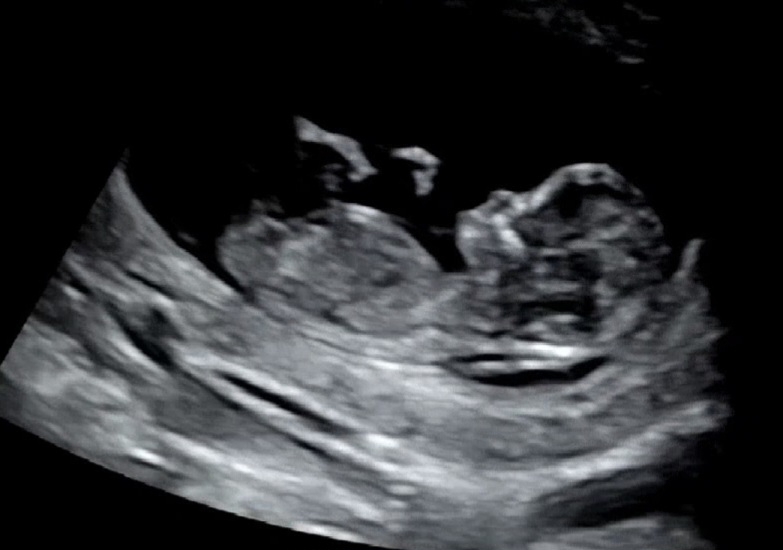

아들일까요? 딸일까요?

너무 궁금하네용ㅎㅎ 각도법 고수님들! 도와주세요🙏 코 뼈 있는거 맞겠죠? 투명대는 안정권이었는데 혹시나해서요 ㅎㅎ

딸...?